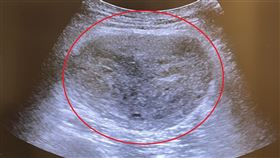

男童肚裡藏著一個人!醫檢查驚:極罕見

家醫科醫師闕壯理在IG發文分享一個極罕見案例,一名1...